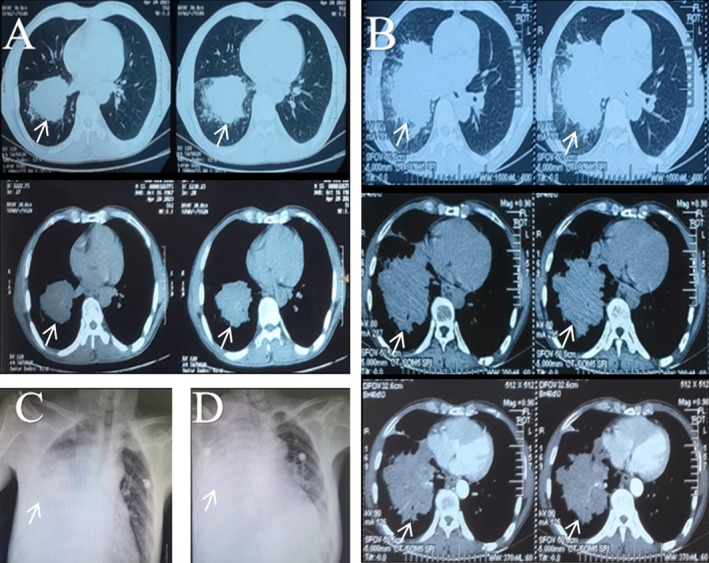

原发性睾丸肺核蛋白(NUT)中线癌(NMC)是一种罕见的恶性肿瘤,其特征与鳞状细胞癌相似,因此容易误诊和漏诊。原发性肺NMC是高度恶性的,与预后差有关,对于不能接受手术的患者没有标准化的有效治疗。同步或顺序放化疗被认为是一种有效的方法,一些靶向药物已经过临床试验并显示出良好的效果。我们报告一例原发性肺部NMC伴颈部淋巴结转移,患者在接受安洛替尼和化疗联合免疫治疗后症状暂时缓解。然而,病情迅速恶化,患者在诊断后1个月内死亡。我们认为,安洛替尼联合化疗以及缩短化疗间隔可有效治疗原发性肺NMC。

Primary pulmonary nuclear protein in testis (NUT) midline carcinoma (NMC) is a rare malignancy with characteristics that resemble those of squamous cell carcinoma, thus making it prone to both misdiagnosis and missed diagnosis. Primary pulmonary NMC is highly malignant and associated with poor prognosis, with no standardised effective treatments for patients who cannot undergo surgery. Concurrent or sequential chemoradiotherapy is considered an effective approach, and some targeted drugs have been clinically tested and demonstrated favourable results. We present a case of primary pulmonary NMC with cervical lymph node metastasis, in which the patient experienced temporary symptom relief after receiving anlotinib and chemotherapy combined with immunotherapy. However, the condition rapidly worsened, and the patient died within 1 month of diagnosis. We believe that combining anlotinib with chemotherapy as well as reducing the chemotherapy interval can be effective in the treatment of primary pulmonary NMC.